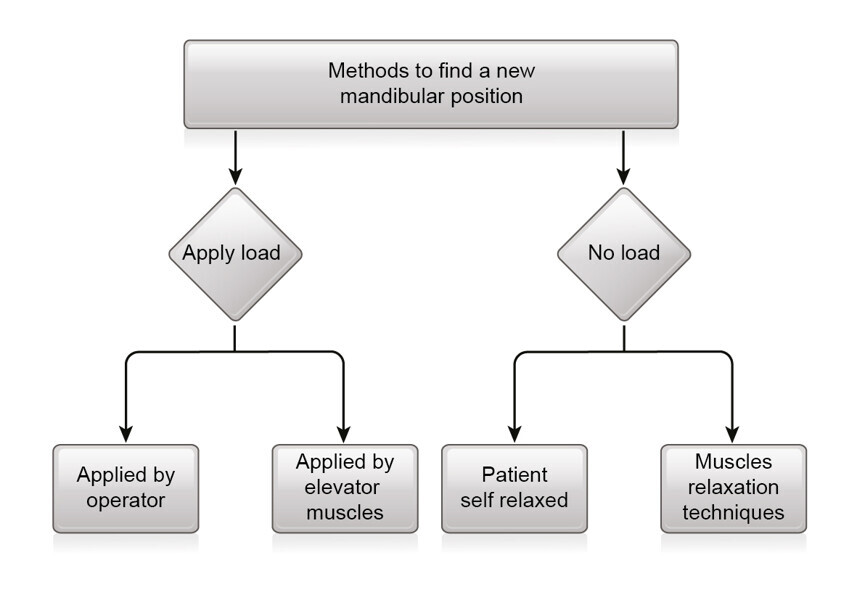

Fig. 6: Methods to find a new mandibular position.